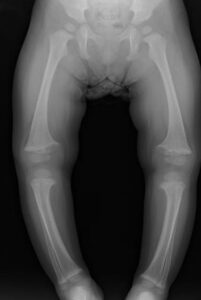

赤ちゃん 内反足 診断-内反足の変形は一般的な状態ですが、この合併症の原因である正確な理由はまだ決定されていません。 内反足は、母親の子宮内での赤ちゃんの位置によって引き起こされる可能性があります。 これは姿勢内反足として知られています。 この状態は、環境 ここでは、息子の先天性内反足の治療や経過をお伝えします。 先天性内反足とはどんな病気? 原因は? 生後6日目に息子の右足首から先が内側に曲がっていることに気付き、受診すると右足先天性内反足と診断されました。

トラブル, 内反小趾, 子どもの足の指, 子供, 対処法, 運動不足 子供は遊び周るのが大好きで、いつも動きまわっていて動き疲れたら寝てしまう。 というのが今までの子どもの姿でした。 しかし最近は、家でゲームをするなどじっとしていて遊ばなくなった診断 整形外科の先生に診ていただきます。先天性内反足を早期に診断して治療を開始することが重要です。 治療 整形外科の先生に治療をしていただきます。 ①治療は早期に開始します。できれば生後1週間。 ②乳児期早期は特殊なギプスを装着します。